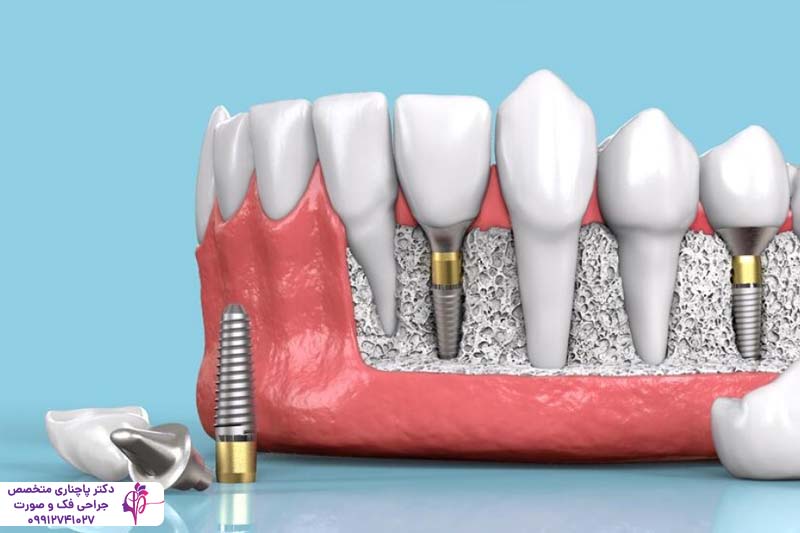

ایمپلنت دندان آلمانی به دلیل دقت مهندسی بالا و استفاده از فناوریهای پیشرفته در طراحی رزوه و سطح فیکسچر، جایگاه ویژهای در بازار جهانی دارد. این ایمپلنتها از تیتانیوم خالص یا آلیاژهای با کیفیت بالا ساخته میشوند که سازگاری مناسبی با استخوان فک دارند. بدنه پایه ایمپلنتهای آلمانی خیلی دقیق طراحی و ساخته میشود. این دقت بالا باعث شده اتصال اولیه با استخوان خیلی بهتر شکل بگیرد و فرآیند استئواینتگریشن با ثبات بیشتری انجام شود.

یک ویژگی مهم ایمپلنت دندان آلمانی تنوع در سیستمهای اتصال و قطعات پروتزی است و به همین دلیل دست دندانپزشکان برای انتخاب بهترین گزینه برای بیمار کاملا باز است. این تنوع بالا باعث شده خیلی از بیماران با شرایط مختلف استخوان فک بتوانند از این ایمپلنتها استفاده کنند. علاوه بر این برندهای ایمپلنت دندان آلمانی و سوئیسی هر دو استانداردهای سختگیرانهای در کنترل کیفیت دارند و همین باعث شده میزان موفقیت درمان با این ایمپلنتها بالا باشد.